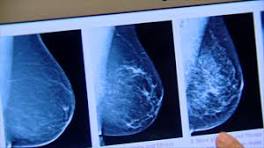

Can Mammograms Spread Cancer? October is breast cancer awareness month, and women are encouraged to get yearly mammograms. Millions of women comply, and are lulled into a ...

Signs and symptoms of breast cancer that can help woman detect the cancer at an early stage INDIANAPOLIS, Ind. (Oct. 3, 2015)-- One out of every eight women will be diagnosed with breast cancer, but there are not always symptoms. Doctors ...